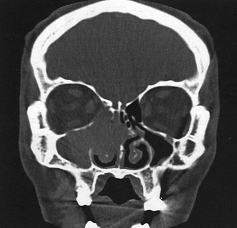

Лицевой череп, придаточные пазухи носа, полость

носа, носоглотка.

КТ позволяет легко визуализировать

дополнительные новообразования в мягких тканях лица, в придаточных пазухах. К

сожалению, во всех этих областях нельзя с достаточной точностью отличить полип

или аденоид от злокачественной опухоли даже при внутривенном контрастировании

(особенно в носоглотке) до появления признаков прорастания в окружающие ткани.

Зато приобретаются точные сведения о местном распространении процесса.

КТ лицевого черепа, пазух